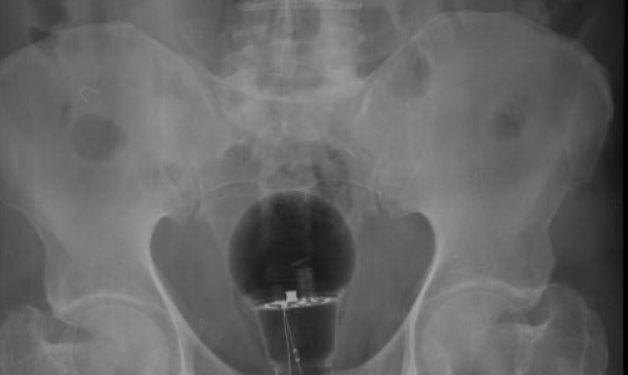

MUNDO – O médico Julian Pylori viralizou no Twitter após revelar que precisou da ajuda de dois colegas para retirar uma lâmpada do ânus de um paciente.

O homem de 53 anos levou três dias para procurar ajuda, após não suportar mais as dores. Ele disse que demorou todo esse tempo por estar com vergonha de contar à esposa o que havia feito.

De acordo com o médico a sorte do paciente é que o objeto era de plástico. Se fosse de vidro teria estourado e poderia ter matado o paciente de hemorragia interna.